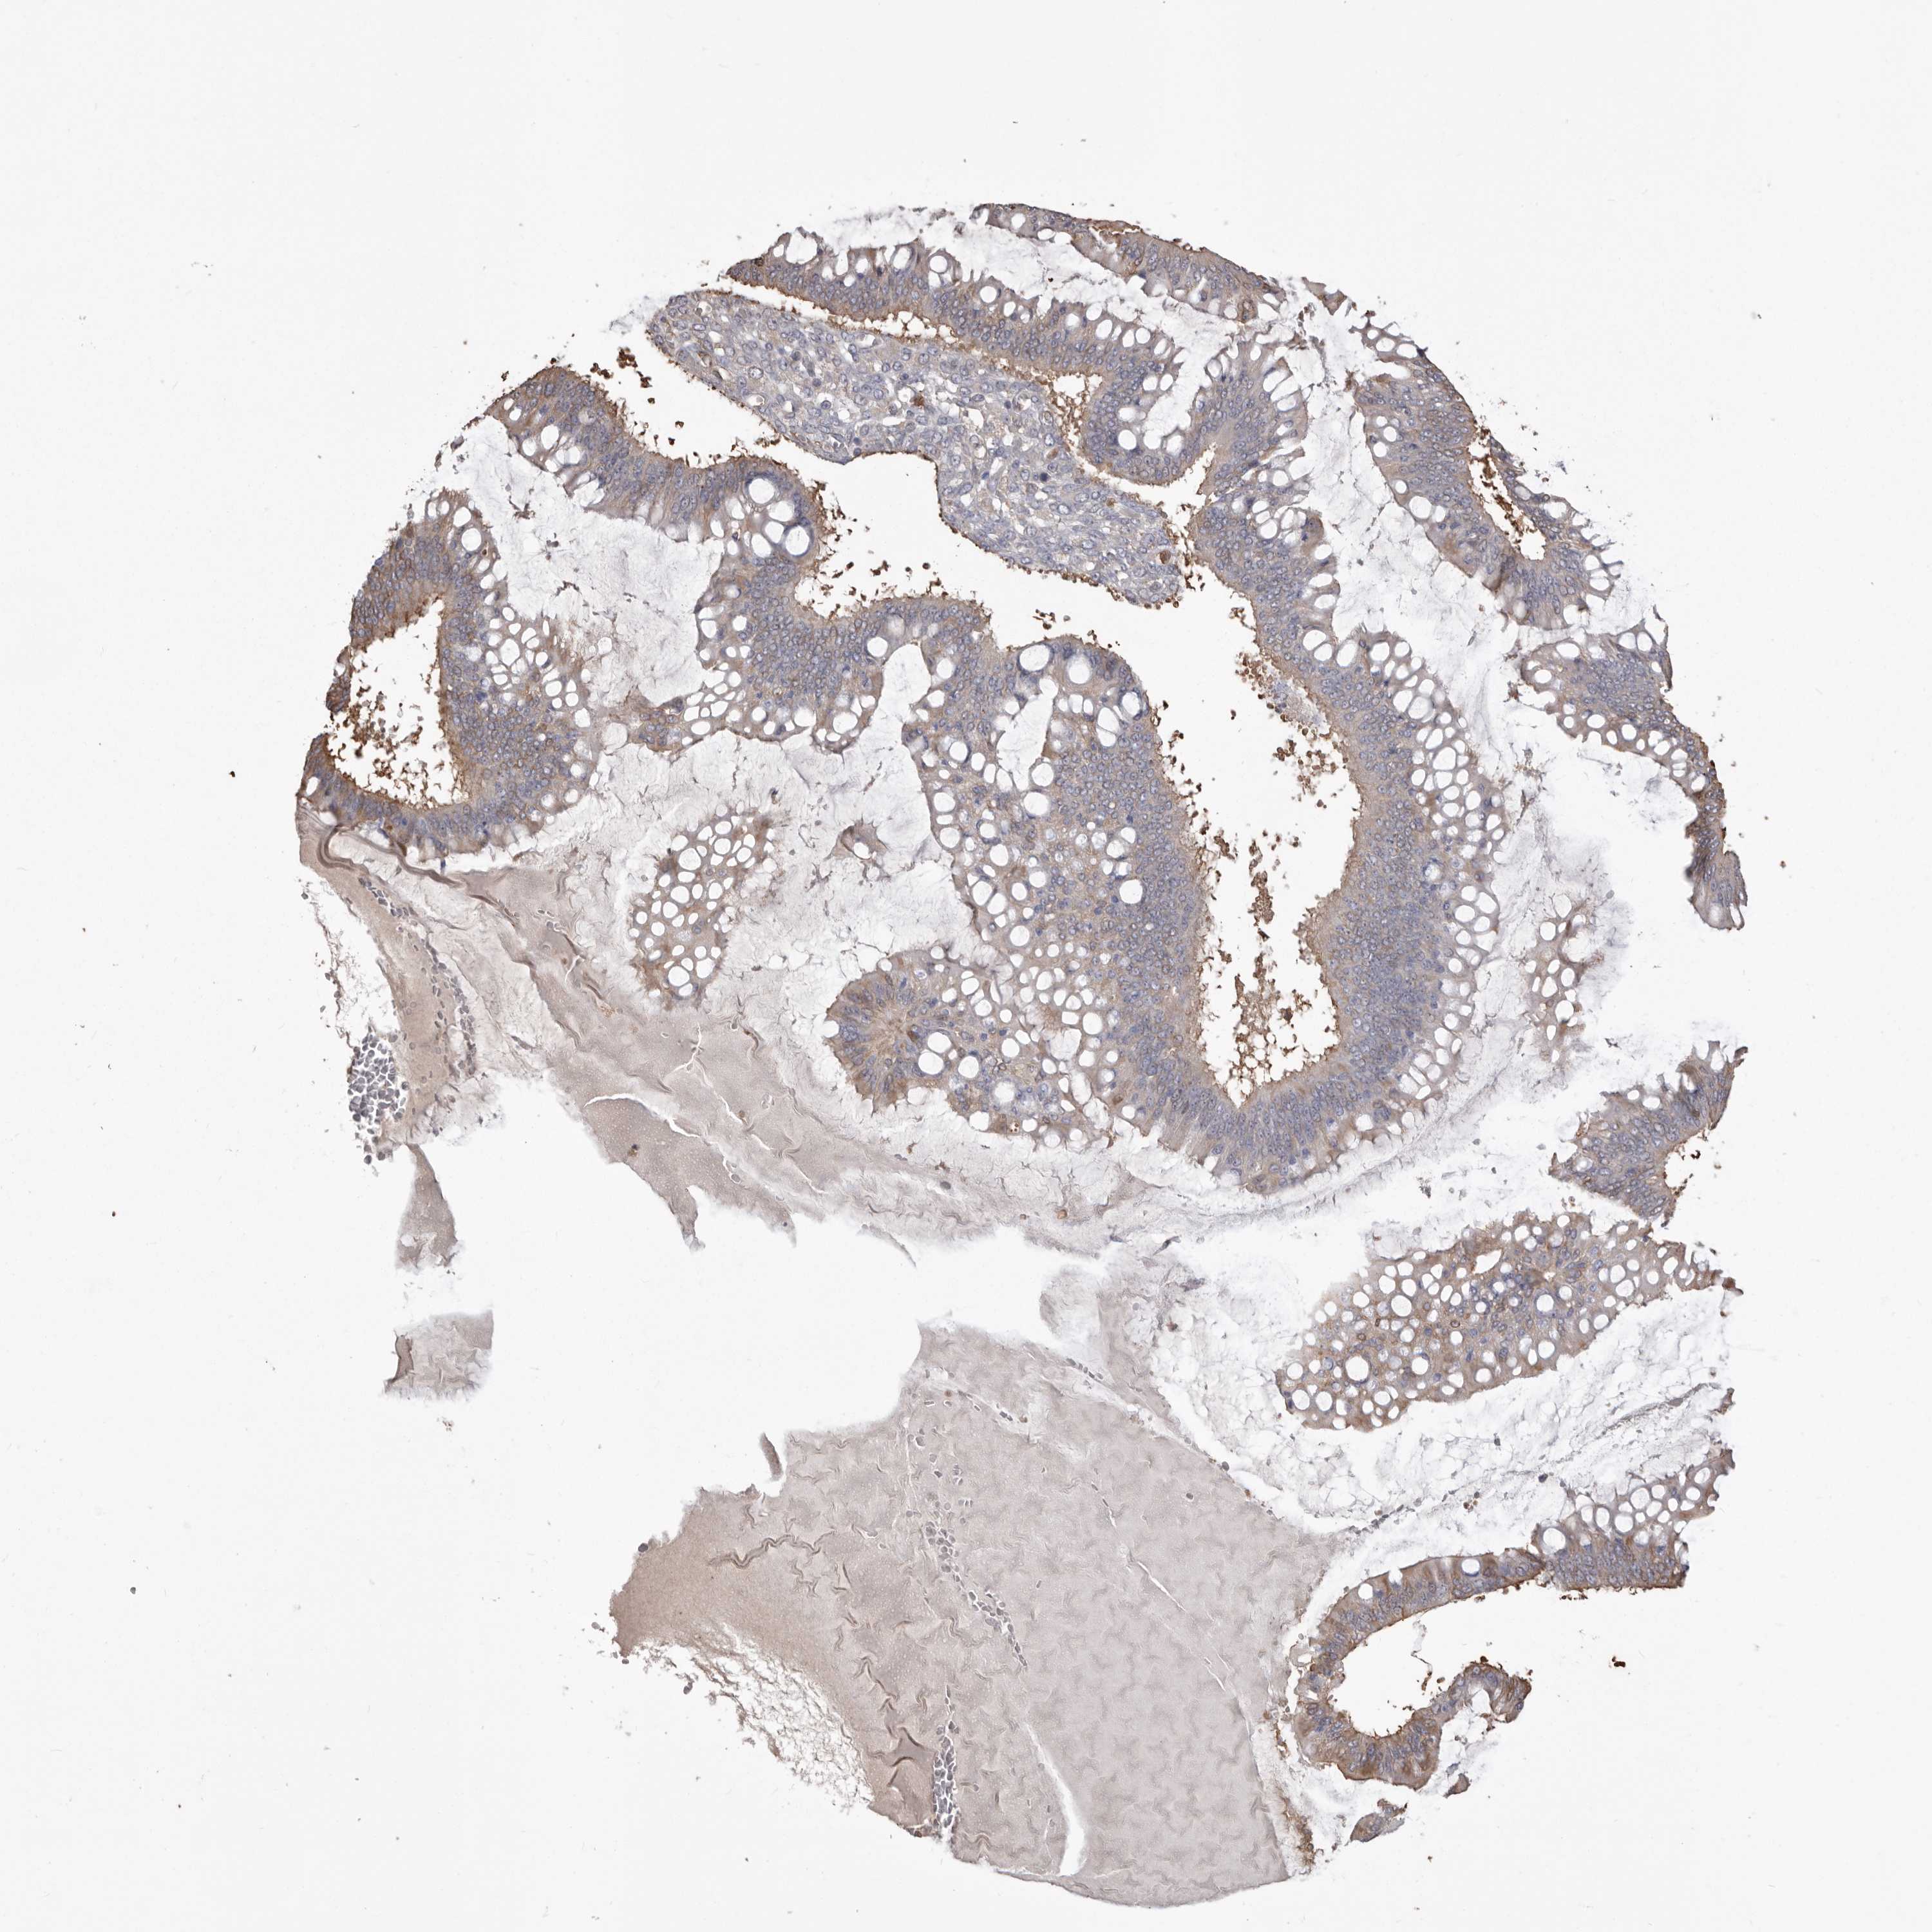

OVARIAN CANCER - Protein expressioni

A mouse-over function shows sample information and annotation data. Click on an image to view it in a full screen mode. Samples can be filtered based on level of antibody staining by selecting one or several of the following categories: high, medium, low and not detected. The assay and annotation is described here.

Note that samples used for immunohistochemistry by the Human Protein Atlas do not correspond to samples in the TCGA dataset.

Antibody stainingi

Antibody staining in the annotated cell types in the current human tissue is reported as not detected, low, medium, or high, based on conventional immunohistochemistry profiling in selected tissues. This score is based on the combination of the staining intensity and fraction of stained cells.

Each image is clickable and will lead to virtual microscopy that enables deeper exploration of all samples and also displays staining intensity scores, fraction scores and subcellular localization as well as patient and tissue information for each sample.

Antibody HPA029501

Antibody CAB019421

Cystadenocarcinoma, serous, NOS

Carcinoma, endometroid

Cystadenocarcinoma, mucinous, NOS

Carcinoma, NOS